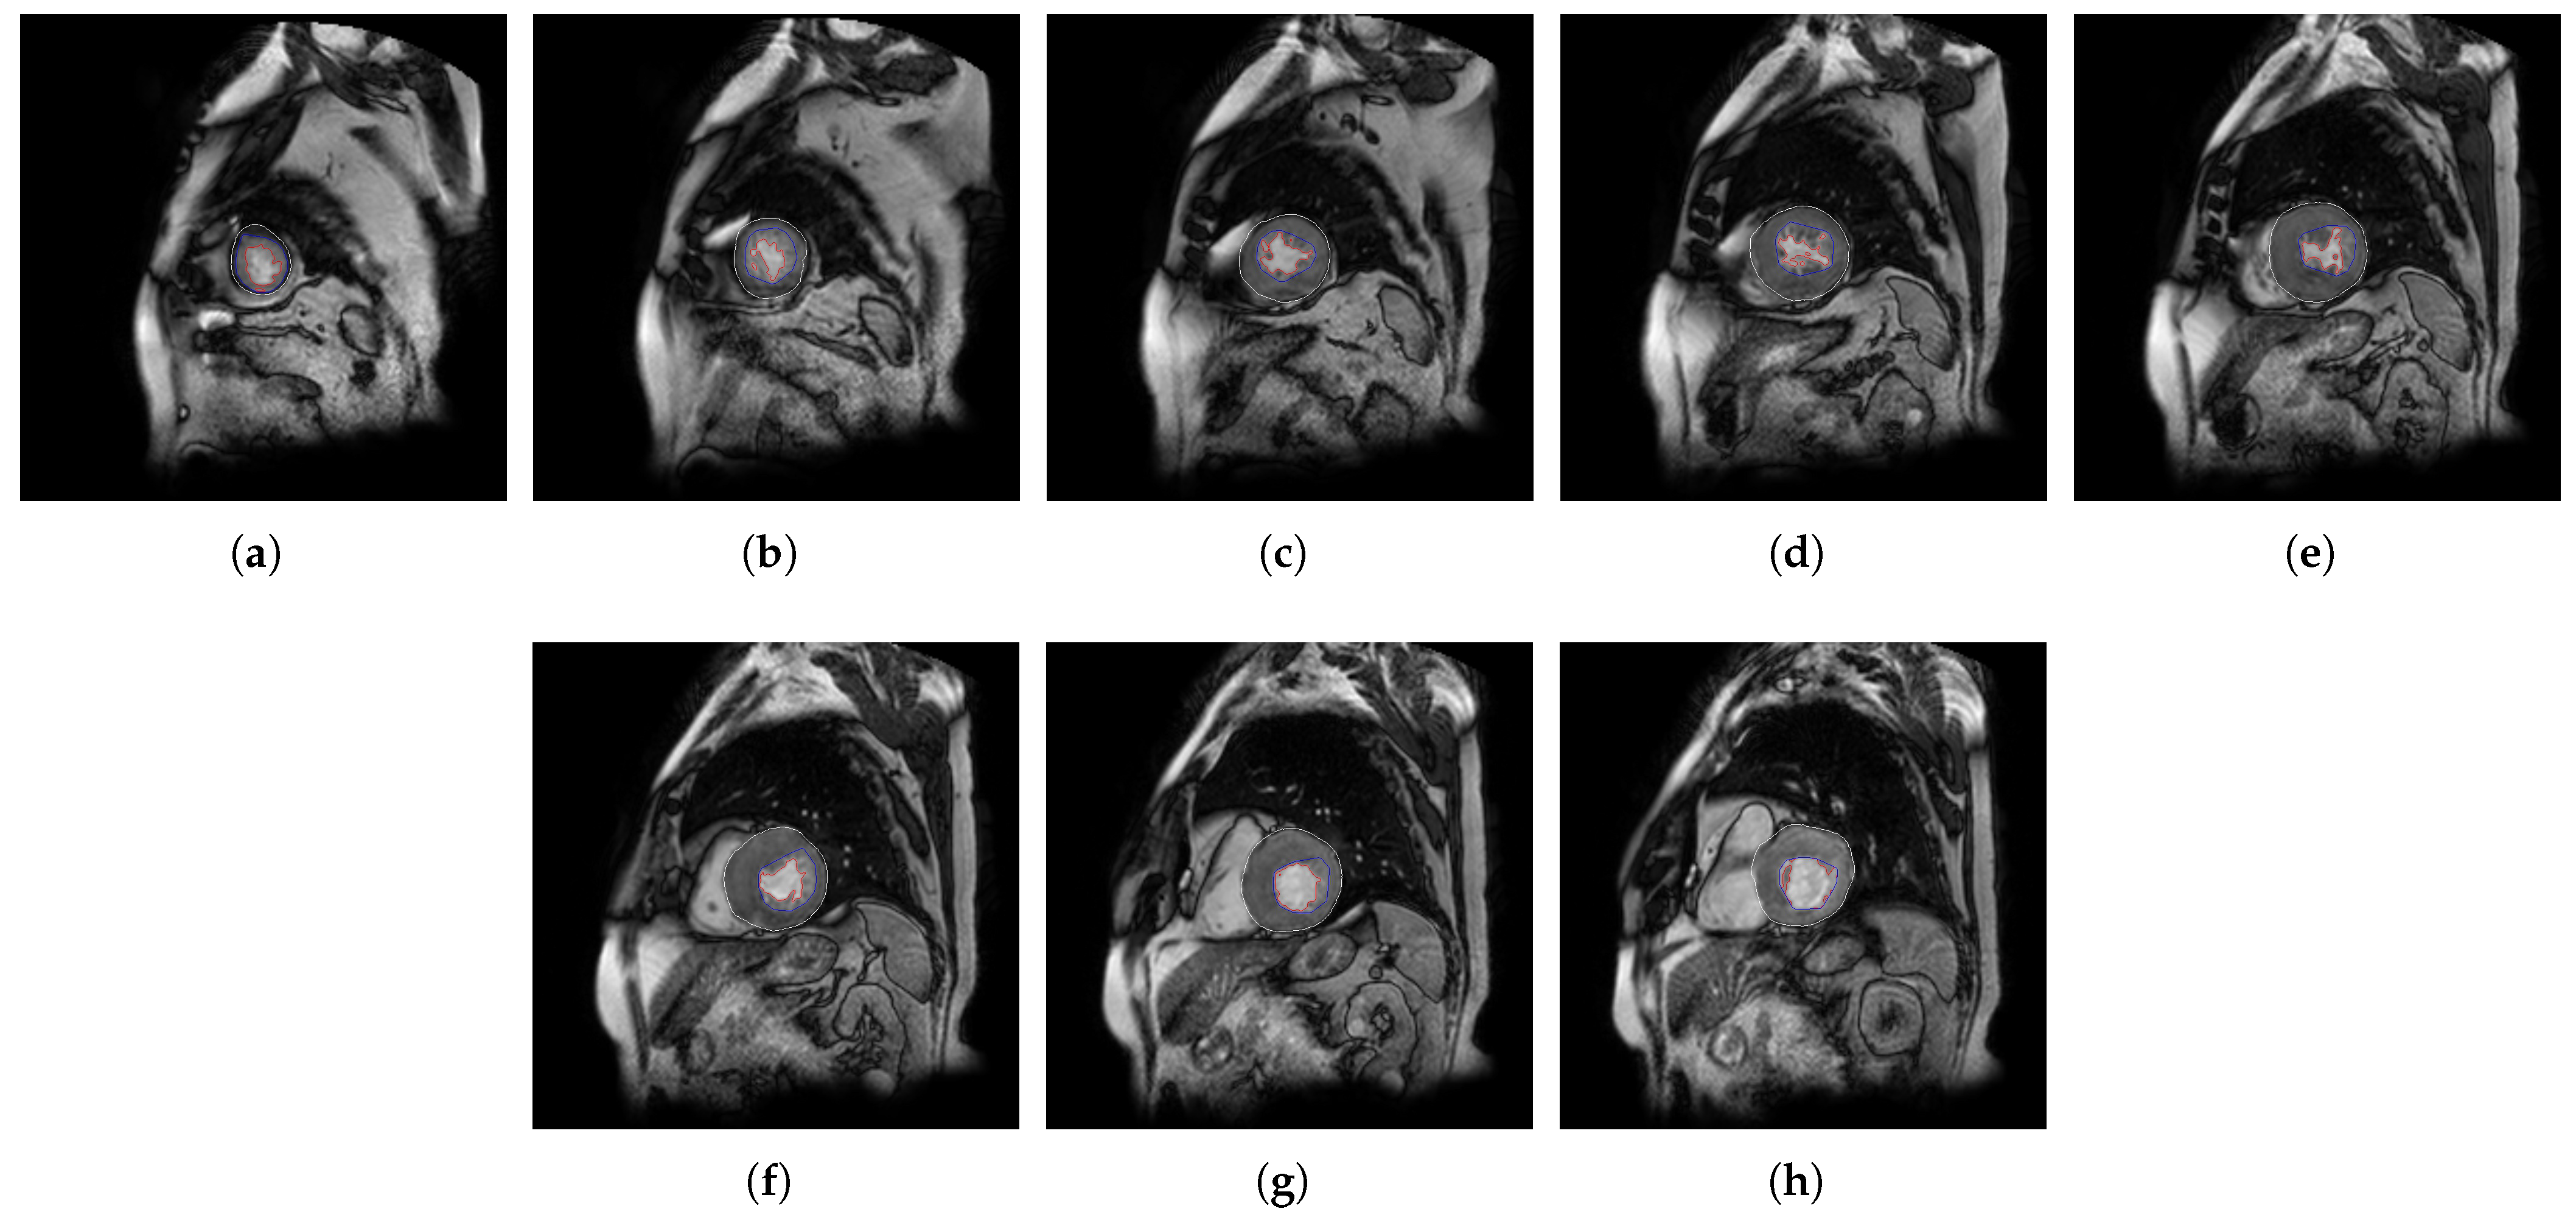

- The different MSERs are detected in a centered ROI of each input image by the use of OpenCV [23]. As the LV cavity is normally represented by a circular shape, the centroid of each MSER detected is computed in order to automatically identify the left ventricle cavity anywhere in the image and for applying the convex hull.

- The previous application of the convex hull allows a second refining to optimize the search process of the external layer and the trabeculae areas. The parameter e-expand is redefined and adjusted to accurately determine the external layer of the compact zone, thanks to plotting several lines from the centroid of the LV to reach the points of the external layer. This parameter establishes the distance of the lines between the centroid of the LV cavity and the possible space where the external layer can be found, taking into account the particular features of genetic cardiomyopathies. We optimized the parameter e-expand for different situations or possible cardiomyopathies.